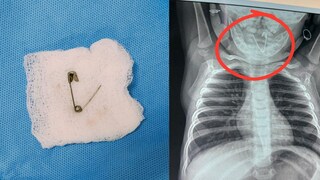

महिना झाला तरी बाळाला सर्दी - खोकल्याचा त्रास होत होता. औषधोपचार केला तरी बाळाचा त्रास कमी होत नसल्याने पालकांनी दापोलीतील बालरोगतज्ज्ञांकडे धाव घेतली. तिथे डॉक्टरांनी एक्स-रे काढण्याचा सल्ला दिला असता, बाळाच्या घशात एक उघडी सेफ्टी पिन अडकल्याचे निदर्शनास आले. परिस्थितीचे गांभीर्य ओळखून डॉक्टरांनी बाळाला तातडीने वालावलकर रुग्णालयात नेण्यास सांगितले.

रुग्णालयात पोहोचताच कान-नाक-घसा विभागाच्या डॉ. सीजा यांनी प्राथमिक तपासणी केली. क्षणाचाही विलंब न लावता बाळावर शस्त्रक्रिया करण्याचा निर्णय घेतला. तपासणीदरम्यान असे लक्षात आले की, आधी घशात दिसणारी ही पिन आता अन्ननलिकेपर्यंत खाली सरकली होती. सर्वात मोठी भीती ही होती की, सेफ्टी पिन उघडी असल्यामुळे ती अन्ननलिकेला छिद्र पाडू शकत होती, जे बाळाच्या जिवासाठी अत्यंत घातक ठरू शकले असते. मात्र, तज्ज्ञ डॉ. राजीव यांनी 'ईसोफॅगोस्कोपी' (Esophagoscopy) या प्रक्रियेद्वारे अत्यंत कौशल्याने ती पिन बाहेर काढली. सात महिन्यांच्या लहान बाळाला भूल देणे हे सर्वात मोठे आव्हान होते, जे रुग्णालयाच्या भूलतज्ज्ञांनी यशस्वीरीत्या पेलले.

शस्त्रक्रियेनंतर बाळाला रुग्णालयातील अद्ययावत बालरोग अतिदक्षता विभागात ठेवण्यात आले होते, जिथे त्याची रिकव्हरी जलद गतीने झाली. कान-नाक-घसा तज्ज्ञ, भूलतज्ज्ञ आणि बालरोगतज्ज्ञ यांच्या एकत्रित प्रयत्नांमुळे हा चमत्कार घडला आहे. अत्याधुनिक यंत्रसामग्री आणि तज्ज्ञ डॉक्टरांमुळे वालावलकर रुग्णालय कोकणातील रुग्णांसाठी खऱ्या अर्थाने वरदान ठरत आहे. अन्ननलिकेत अडकलेली उघडी सेफ्टी पिन अत्यंत गुंतागुंतीच्या शस्त्रक्रियेद्वारे बाहेर काढून डॉक्टरांनी या बाळाला मृत्यूच्या दाढेतून सुखरूप बाहेर काढले आहे.